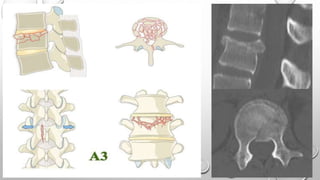

Tipo A

Describen daño del cuerpo vertebral sin

compromiso de la banda de tensión.

A0: Fractura no estructural, menor

A1: Compresión en cuña

A2: Separación, División

A3: Estallido incompleto

A4: Estallido Completo